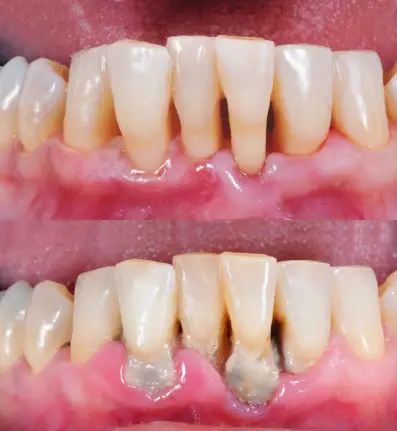

잇몸에 갇힌 박테리아와 음식 부스러기가 축적되어 구취가 남을 수 있습니다. 건강한 잇몸은 분홍색이며 단단해야 합니다. 잇몸이 붉어지거나 부어 오르면, 이는 플라크 축적으로 인한 감염의 징후일 수 있습니다.

| 분홍색, 단단한 잇몸 | 건강한 상태 |

| 붉은 잇몸 | 플라크 축적으로 인한 감염 징후 |

| 부은 잇몸 | 감염이 심각한 상태 |

이와 같은 증상이 나타날 경우, 치과 의사를 방문하여 적절한 치료를 받는 것이 중요합니다. 잇몸 건강은 전체적인 건강에 큰 영향을 미치므로 꾸준한 관리가 필수적입니다.잇몸병은 흔하고 중요한 구강 질환입니다. 잇몸의 혈관이 염증을 일으키면, 잇몸이 붉게 발적하거나 출혈할 수 있습니다. 치은염은 잇몸병 중 가장 흔한 것으로, 초기 단계에서 치아 주변을 둘러싸고 있는 섬유로 덮인 조직의 염증을 나타냅니다. 피가 나지 않는 건강한 잇몸은 무엇보다도 중요합니다. 정기적인 칫솔질과 구강 세안은 잇몸병을 예방하고 조기 발견할 수 있습니다.

- 잇몸병은 잇몸이 붉거나 출혈하는 상황을 두고 일반적으로 사용됩니다.

- 치은염은 잇몸병 중 가장 흔한 형태로서, 잇몸 주변 조직의 염증을 나타냅니다.

- 건강한 잇몸에서는 피가 나지 않아야 하며, 치은염의 초기 징후 중 하나로 지속적인 출혈이 있습니다.